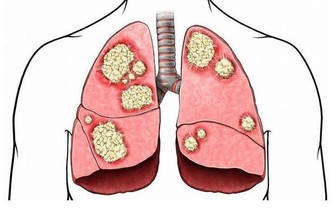

五種吃飯方式易引發胃癌

1、吃得過飽

《黃帝內經》裡面說了句非常經典的話:“飲食自倍,腸胃乃傷。”說明一次吃很多東西,首先損傷的是我們自己的腸胃。中醫古書《濟生方》也指出:“過餐五味,魚腥乳酪,強食生冷果菜停蓄胃脘……久則積結為症瘕。”從古人的經驗看,飲食過量就會使腸胃功能 失調,時間久了,生病得癌也無法避免。

2、少吃蔬果

膳食講究平衡,蔬菜水果是我們日常膳食中的重要組成部分,所以,如果平時只愛吃肉,不愛吃蔬菜和水果,就增加了患癌的風險性。研究表明:長期大量攝入紅肉和熟肉製品分別使結腸癌危險增加29%和50%。

3、吃得過快

吃 東西狼吞虎嚥仿佛成為這個時代上班族的一個通病,工作和生活的壓力讓上班族處於一個高度緊張的狀態中,吃飯好像只是為了簡單的身體需要,所以,吃飯速度非 常快。實際上這樣對身體健康非常不利。吃飯快,食物的咀嚼不細,易損傷消化道黏膜,產生慢性炎症;另外,吃飯快,食物團塊的體積大,易對食道和賁門等消化 道產生較強的機械刺激,久之會引起消化道損傷甚至癌變。

4、吃滾燙的食物

臨床中,醫生發現很多消化系統癌症患者,特別是食管癌、胃癌患者,他們有一個共同的特點,就是喜歡吃非常熱的食物,每頓飯都恨不得吃那些剛出鍋的東西。諮詢一位元被確診為食管癌的患者飲食情況,發現他平日不但喜歡吃燙嘴的飯菜,還非常喜歡喝熱茶,就是這些不良的飲食習慣,造成他中年發病。

5、飲酒過多超量

從保健方面講,適量飲酒能興奮神經,讓人產生愉悅的感覺,有提神醒腦、舒筋活血的生理功能,可以鬆弛血管,改善血液迴圈,提高人體免疫力,增進食欲,有利於睡眠。最近,國外的研究分析顯示,每日飲酒少於20克,可使冠心病風險降低20%,在糖尿病、高血壓、陳舊性心肌梗死病人中,也得到同樣結果。